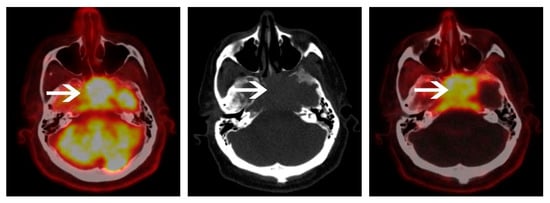

| Areas of impaired detection | -FL of right lower ribs: “liver shadowing” -Liver EMD | Skull FL: “brain shadowing” |